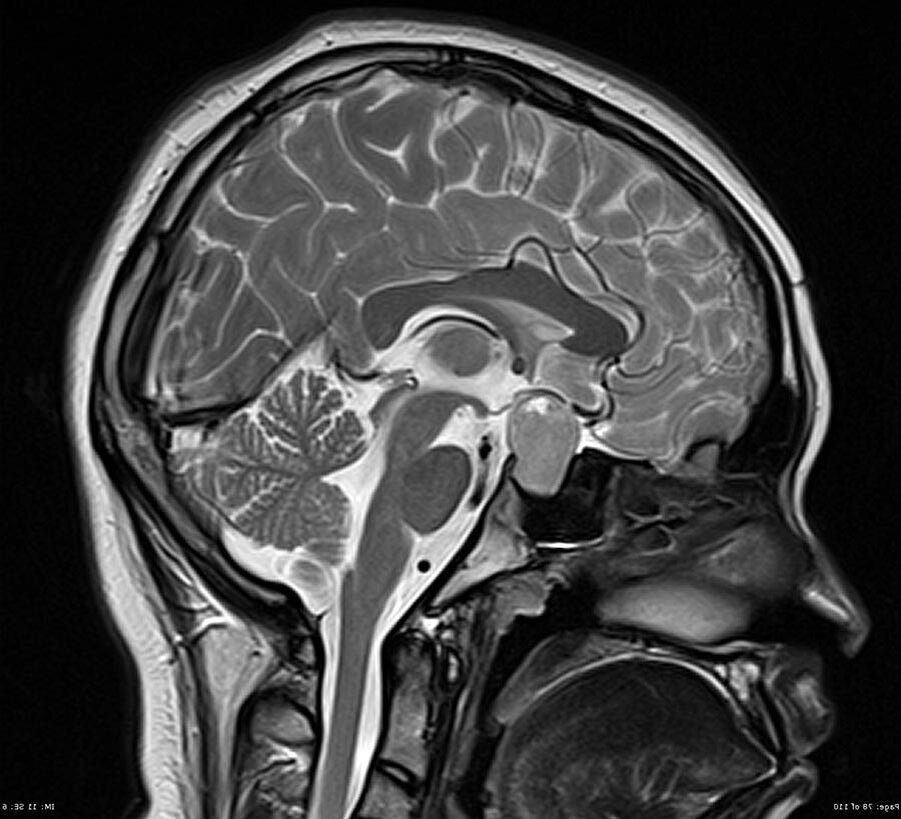

МРТ гипофиза – это узконаправленный, прицельный метод диагностики гипофиза и тканей головного мозга, находящихся в зоне турецкого седла. Сложность обнаружения изменений в питуитарной железе способом объясняется его местом нахождения в основании головного мозга и маленькими размерами в диапазоне от 15 до 17 мм. Гипофиз играет важную роль в функционировании эндокринной системы человека. Орган отвечает за выработку гормонов, влияет на рост и обменные процессы в организме человека. Опухолевые образования в зоне гипофиза, например, микро или маркоагеномы могут приводить к гормональным сбоям. По этой причине корректная и быстрая их диагностика играет важную роль поддержания здоровья человека.

Исследование микроаденомы гипофиза – достаточно частая процедура, которая представляет собой диагностику доброкачественной опухоли передней доли железы гипофиза. Аденокарциномы, злокачественные образования тоже исследуют на аппарате МРТ, но встречаются они гораздо реже. Аденомы, особенно небольшого размера, лучше всего видны на тех изображениях, которые были сделаны с использованием контраста. Дело в том, что новообразованиям сопутствует густая сетка кровеносных сосудов, и это позволяет на томографии найти даже самые микроскопические аденомы. Также контрастный препарат позволяет определить точные границы образования, определить степень его взаимодействия с окружающими тканями, а также определить его структуру и тип.

МРТ гипофиза и головного мозга - это два различных вида магнитно-резонансной томографии. Исследования питуитарной железы и головного мозга могут быть вообще не связаны между собой. Однако возможны ситуации, когда врачи назначают комплексное обследование, когда у пациента есть выраженная эндокринная патология, например, синдром Иценко-Кушинга, или при дисциркуляторной энцефалопатии и опухолях мозга с множественными очагами поражения.